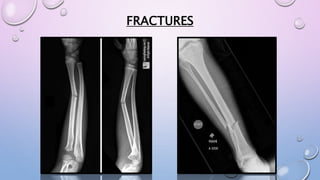

SHAFT TIBIA AND FIBULA FRACTURE

• XRAY OF LEG AP/ LAT

• IMMOBILIZATION- ABOVE

KNEE SLAB